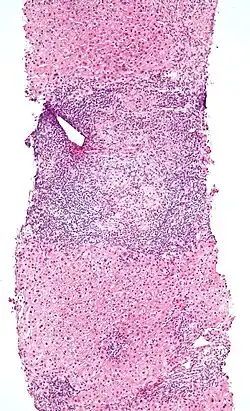

Low-magnification micrograph of PBC, H&E stain -

On microscopic examination of liver biopsy specimens, PBC is characterized by chronic, nonsuppurative inflammation, which surrounds and destroys interlobular and septal bile ducts. These histopathologic findings in primary biliary cholangitis include:[32]

- Inflammation of the bile ducts, characterized by intraepithelial lymphocytes

- Periductal epithelioid granulomas.

- Proliferation of bile ductules

- Fibrosis (scarring)

The Ludwig and Scheuer scoring systems have historically been used to stratify four stages of PBC, with stage 4 indicating the presence of cirrhosis. In the new system of Nakanuma, the stage of disease is based on fibrosis, bile duct loss, and features of cholestasis, i.e. deposition of orcein-positive granules, whereas the grade of necroinflammatory activity is based on cholangitis and interface hepatitis. The accumulation of orcein-positive granules occurs evenly across the PBC liver, which means that staging using the Nakanuma system is more reliable regarding sampling variability.

Histopathology stages (by Ludwig and Scheuer systems)

- Stage 1 – portal stage: Normal-sized triads, portal inflammation, subtle bile duct damage: Granulomas are often detected in this stage.

- Stage 2 – periportal stage: Enlarged triads, periportal fibrosis and/or inflammation, typically characterized by the finding of a proliferation of small bile ducts

- Stage 3 – septal stage: Active and/or passive fibrous septa

- Stage 4 – biliary cirrhosis: Nodules present, garland or jigsaw puzzle pattern